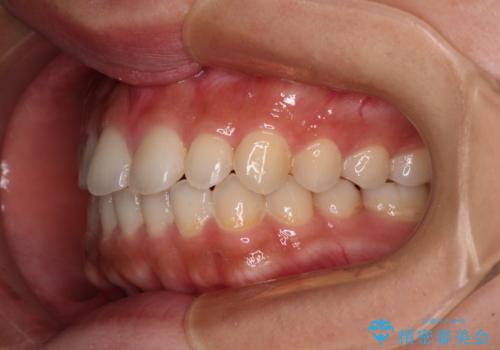

- インビザライン・ライト

- 1年5ヶ月

インビザライン・ライトは、製作できるアライナーの枚数に制限があるため、移動可能な量に限りがあります。

一方で、半年から1年程度で治療を終えることができるため、軽度の歯列不正の患者様には大変お勧めです。